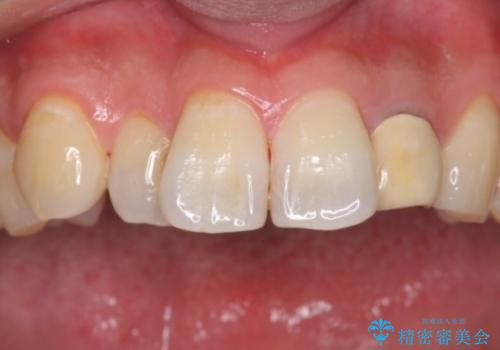

- 結婚式を控えており、それまでに歯を白くしたいということで来院されました。

歯医者に来院するのが久しぶりの様で歯の表面に汚れが付着しているとホワイトニング薬剤の効果が薄れるため、術前のクリーニングをおすすめしその後オフィスホワイトニングエクセレントコースを行いました。

全体的にトーンアップしました。オフィスホワイトニングはホームホワイトニングに比べ1度で白くなりやすいため、直近の予定を控えている方にお勧めしております。